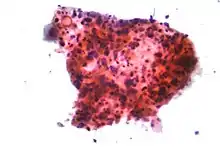

_by_core_needle_biopsy.jpg.webp)

În cazul unui cancer bronho-pulmonar microcelular (CBPM), celulele conțin granule neurosecretoare dense (veziculecare conțin hormoni neuroendocrini), ceea ce îi conferă acestei tumori o asociere cu sindromul endocrin/paraneoplazic.[50] Majoritatea cazurilor apar în căile respiratorii mai mari (bronhiile primare și secundare]).[13] Aceste cancere se dezvoltă rapid și se extind la începutul bolii. 60-70 % dintre cazuri prezintă metastaze. Acest tip de cancer pulmonar este puternic asociat cu fumatul.[4]